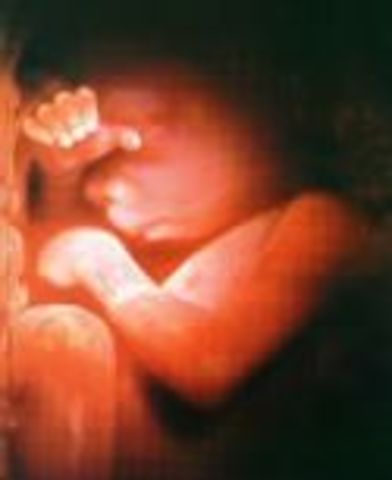

• Week Twenty Four: Practices Breathing

Week Twenty Four: Practices Breathing

The eyelids are clearly seen at this point. The baby can be birth at this time with a chance to survive.